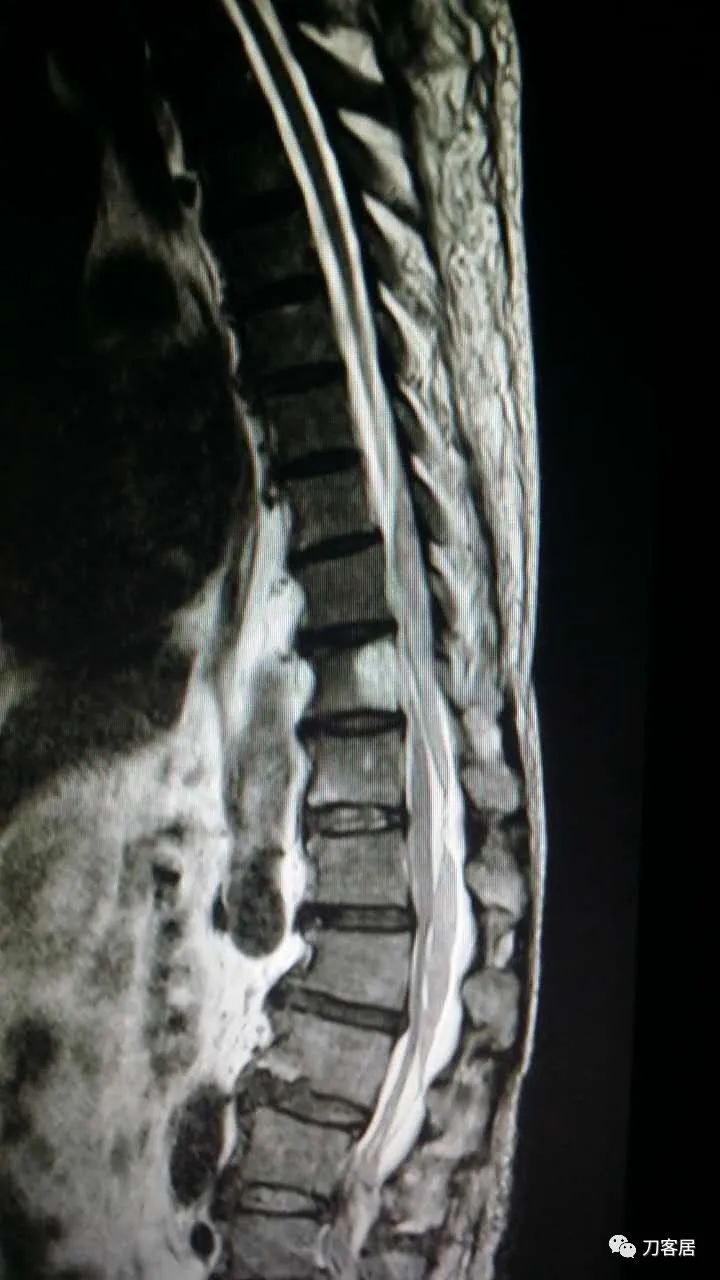

加注图10: 腰1-2椎管内后方可见梭形占位信号改变。

加注图11. 腰1-2椎管内后方可见梭形占位信号改变。

加注图21. MRI显示胸9-10和腰1-2椎管内后方占位病变,考虑血肿形成。

加注图22. MRI显示胸9-10和腰1-2椎管内后方占位病变,考虑血肿形成。